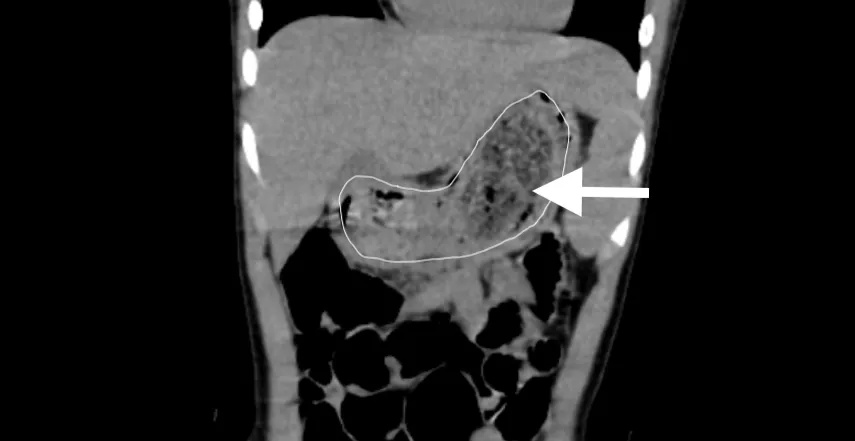

CT检查呈现明明胃内有巨大的毛发石

明明家长于是带明明来到中山大学孙逸仙纪念医院。明明在接受腹部CT检查后,该院小儿外科主任邓小耿教授团队决定为其实施单孔腹腔镜下胃切开取巨大毛发石术。手术过程顺利,明明术后恢复良好,无并发症,并在手术后1周出院。